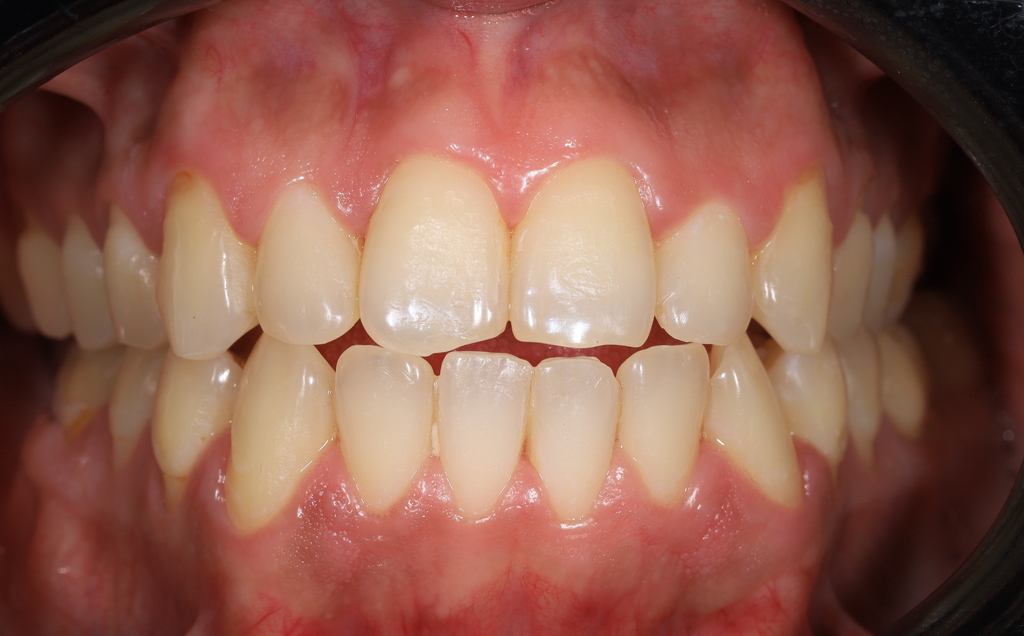

Zaprezentujemy serię poruszających historii pacjentów, którzy zdecydowali się na kompleksowe leczenie dentystyczne. Od przypadków zaawansowanej próchnicy, przez wypadki, które wymagały rekonstrukcji zębów, po pacjentów marzących o hollywoodzkim uśmiechu dzięki zastosowaniu licówek – każda historia jest dowodem na to, jak nowoczesna stomatologia może odmienić życie.

Skupimy się na innowacyjnych technologiach i metodach leczenia stosowanych w naszej klinice, które sprawiają, że te metamorfozy są możliwe. Od cyfrowego projektowania uśmiechu (DSD), przez ortodoncję i implanty, po zaawansowaną chirurgię szczękowo-twarzową. Omówimy, jak te techniki pracują razem, aby osiągnąć najlepsze wyniki.

Poprawa estetyki uśmiechu: wybielanie zębów.